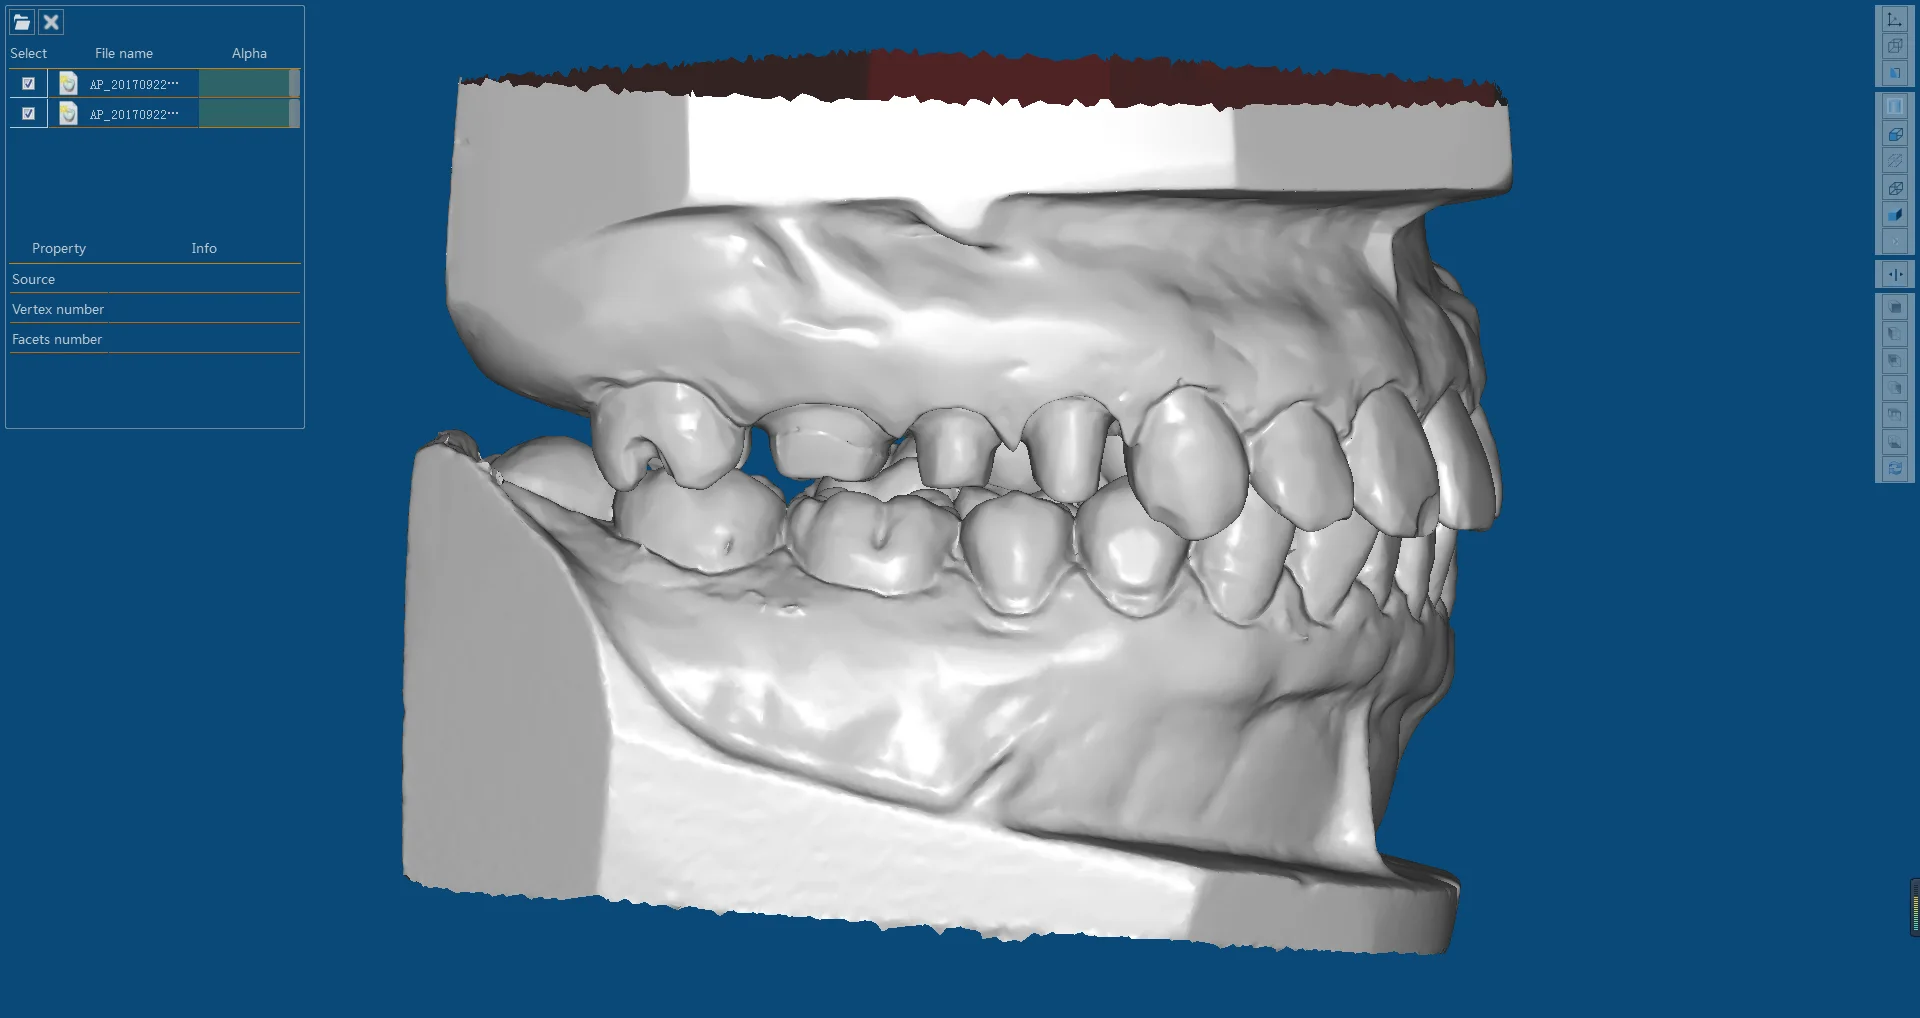

Dis Hekimliginde Cad Cam Uygulamalari Teknik Ressamin Blogu

Sabit Protezler Bolum 9 2 Cad Cam Ve Freze Teknolojisi